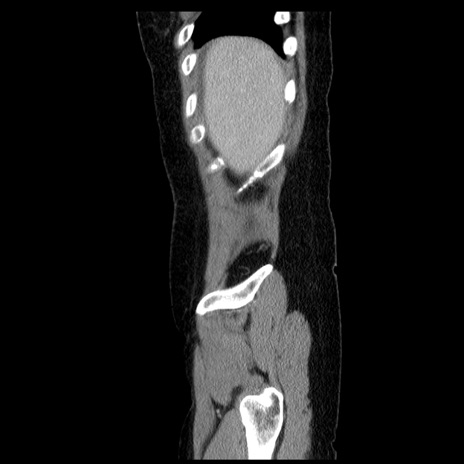

症例6(矢状断像)

【症例】50歳代女性

【主訴】下腹部痛

【現病歴】本日朝より下痢2回あり。 昼食を食べた後、嘔吐3回、下腹部痛認め、症状軽快せず、当院救急搬送。

最終食事:本日昼(生ものなし)。 昨日の夜、刺身を食ぺたとのこと。周囲に同様の症状の者なし。普段、排便は毎日あるとのこと。

【既往歴】卵巣癌術後(8年前に当院で卵巣摘出)

【身体所見】 意識清明、腹部:平坦、腸蠕動音→、やや硬、下腹部自発痛・圧痛あり、反跳痛あり、筋性防御なし。

【データ】WBC 16000、CRP 0.01